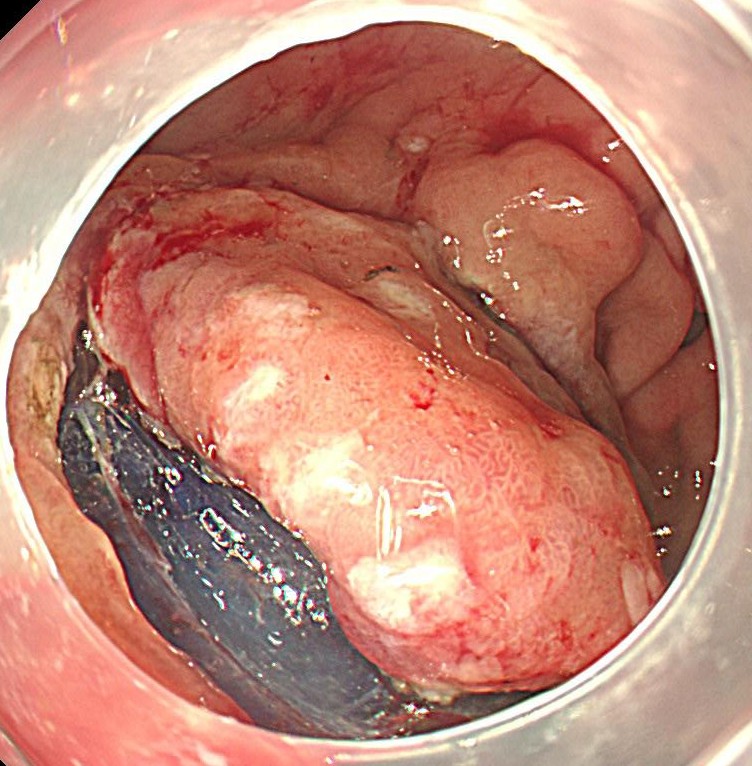

前庭部に中心陥凹、周囲発赤するIIA+IICがん部を認めます。

NBI(狭帯域光観察)を用いると腫瘍の不整像がはっきりわかります。

がん部を取り囲むようにマーキングをします。フラッシュナイフ2.5を用いています。電気メスはVIO300を使用しています。